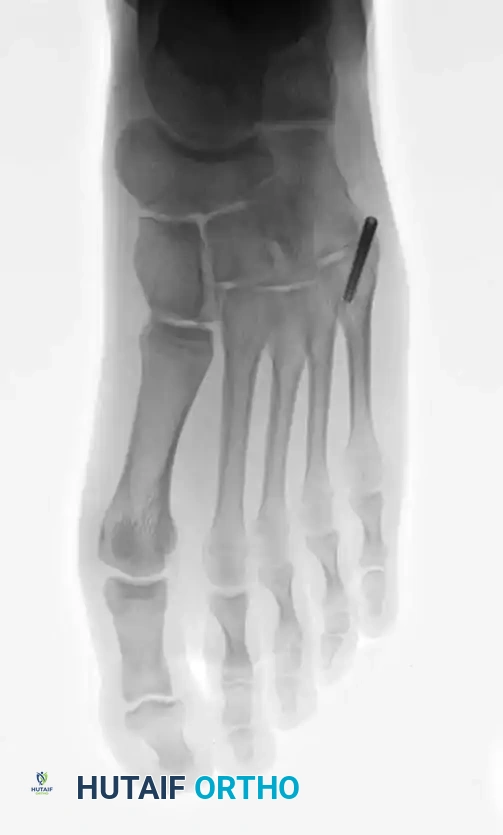

METATARSALS Surgical Diagram

Fig. 86-45 A-C. Type IA (DeLee) fifth metatarsal fracture in a collegiate soccer player, representing an ideal candidate for early intramedullary fixation.

Fig. 86-45 A-C, Type IA (DeLee) fi fth metatarsal fracture in collegiate soccer player. D-F, After fi xation with variable pitch compression screw.

Fig. 86-45 D-F. Postoperative imaging after robust fixation utilizing a variable pitch compression screw, ensuring excellent compression across the fracture site.